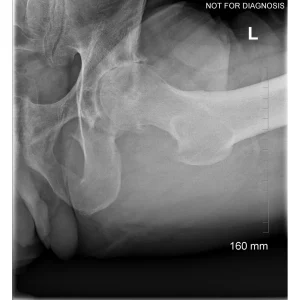

Hip resurfacing is a type of hip surgery used to treat hip arthritis, most commonly in younger and more active patients. Unlike a total hip replacement, hip resurfacing preserves more of your natural thigh bone. Instead of removing the entire femoral head (ball at the top of the thigh bone), the damaged surface is trimmed and covered with a smooth metal cap. The hip’s socket on the pelvis is also fitted with a metal cup.

- Have good bone quality and strong femoral neck bone

- Have a larger femoral head size

Dr Grammatopoulos will review your X-rays and other imaging carefully to determine whether hip resurfacing is an appropriate option for you.